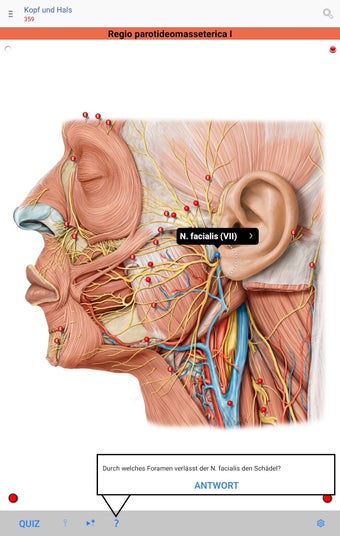

The app consists of different sections, each of which contains information about a specific part of the body. You will learn about the different organs, as well as the muscles, bones, and other important structures. You can test yourself with a unique quiz that consists of multiple-choice questions.